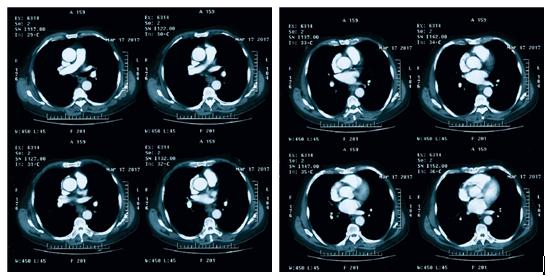

胸部CT增强:食管胸段增厚,左心房水平食道腔内结节,考虑肿瘤性病变; 纵隔内多发淋巴结,部分饱满;双侧胸膜增厚;两肺间质纹理增多,两肺气肿(图4)

图4

上腹部CT增强:食管胸段增厚,左心房水平食道内软组织结节,局部管腔变窄;胆囊未见显示;双侧肾上腺外侧肢稍饱满;十二指肠憩室;肝胃韧带区及腹主动脉旁多发小淋巴结,部分稍饱满(图5)

图5